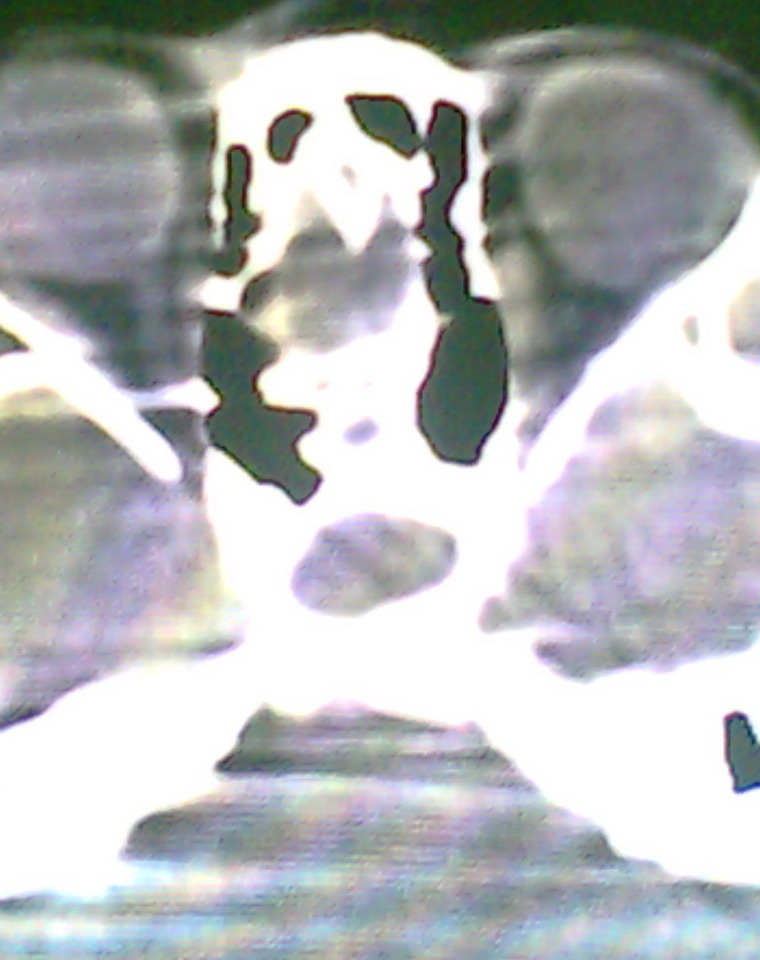

女、18岁,身高1.5左右,鼻塞、流涕数月,两侧瞳孔明显增大,曾与几年前去北京看眼,未发现病变。

考虑起源与蝶窦的粘液囊肿。

支持:考虑起源与蝶窦的粘液囊肿,应该加冠状面扫描

考虑脑膜脑脊液鼻内膨出

考虑起源于蝶窦的粘液囊肿突入鼻咽部。

\"几年前去北京看眼\"不知这句话有何玄机,支持考虑脑膜脑脊液鼻内膨出,膨出口在蝶鞍处

建议冠状面扫描,支持:脑膜鼻内膨出; 蝶窦粘液囊肿突入鼻腔可能性小。

在上级医院冠状位ct扫描后,诊断为:脑膜膨出,已住院准备手术。等待术后结果。